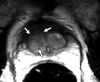

Purpose: To analyze the diffusion and perfusion parameters of central gland (CG) prostate cancer, stromal hyperplasia (SH), and glandular hyperplasia (GH) and to determine the role of these parameters in the differentiation of CG cancer from benign CG hyperplasia.

Materials and methods: In this institutional review board-approved (with waiver of informed consent), HIPAA-compliant study, 38 foci of carcinoma, 38 SH nodules, and 38 GH nodules in the CG were analyzed in 49 patients (26 with CG carcinoma) who underwent preoperative endorectal magnetic resonance (MR) imaging and radical prostatectomy. All carcinomas and hyperplastic foci on MR images were localized on the basis of histopathologic correlation. The apparent diffusion coefficient (ADC), the contrast agent transfer rate between blood and tissue (K(trans)), and extravascular extracellular fractional volume values for all carcinoma, SH, and GH foci were calculated. The mean, standard deviation, 95% confidence interval (CI), and range of each parameter were calculated. Receiver operating characteristic (ROC) and multivariate logistic regression analyses were performed for differentiation of CG cancer from SH and GH foci.

Results: The average ADCs (× 10(-3) mm(2)/sec) were 1.05 (95% CI: 0.97, 1.11), 1.27 (95% CI: 1.20, 1.33), and 1.73 (95% CI: 1.64, 1.83), respectively, in CG carcinoma, SH foci, and GH foci and differed significantly, yielding areas under the ROC curve (AUCs) of 0.99 and 0.78, respectively, for differentiation of carcinoma from GH and SH. Perfusion parameters were similar in CG carcinomas and SH foci, with K(trans) yielding the greatest AUCs (0.75 and 0.58, respectively). Adding K(trans) to ADC in ROC analysis to differentiate CG carcinoma from SH increased sensitivity from 38% to 57% at 90% specificity without noticeably increasing the AUC (0.79).

Conclusion: ADCs differ significantly between CG carcinoma, SH, and GH, and the use of them can improve the differentiation of CG cancer from SH and GH. Combining K(trans) with ADC can potentially improve the detection of CG cancer.